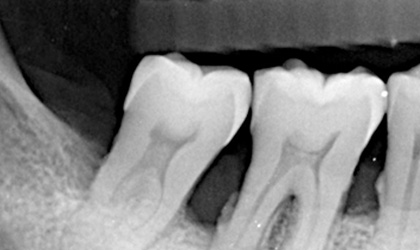

| X光檢查 | 硬組織型態 |